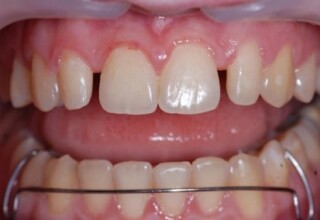

Restoration of bilateral diastemas between central and lateral incisors.

Diastemas were created mainly because of narrow laterals. After orthodontic treatment was finalized, the diastemas were closed with two composite resin restorations.